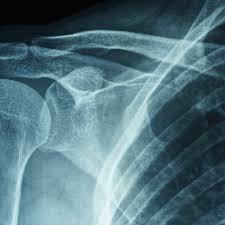

③ 영상 검사

- X-ray: 다른 질환(석회성 건염, 관절염 등) 배제

- MRI: 관절낭 염증 및 유착 확인